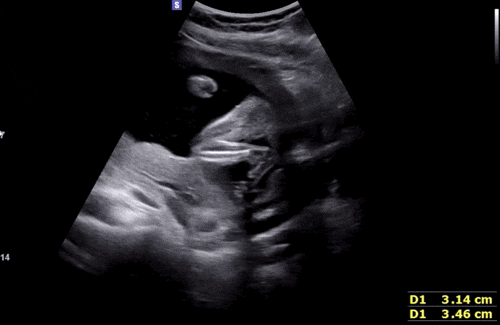

[임신 22주차 기록] 정밀초음파 / 태동검사 / 코베 / 청모 / 임산부석 싸움난 썰

정밀초음파도 보고 베이비페어도 가고 청첩장 모임도 하며 은근 외출이 잦았던 22주차 기록✨ <22주 0일...